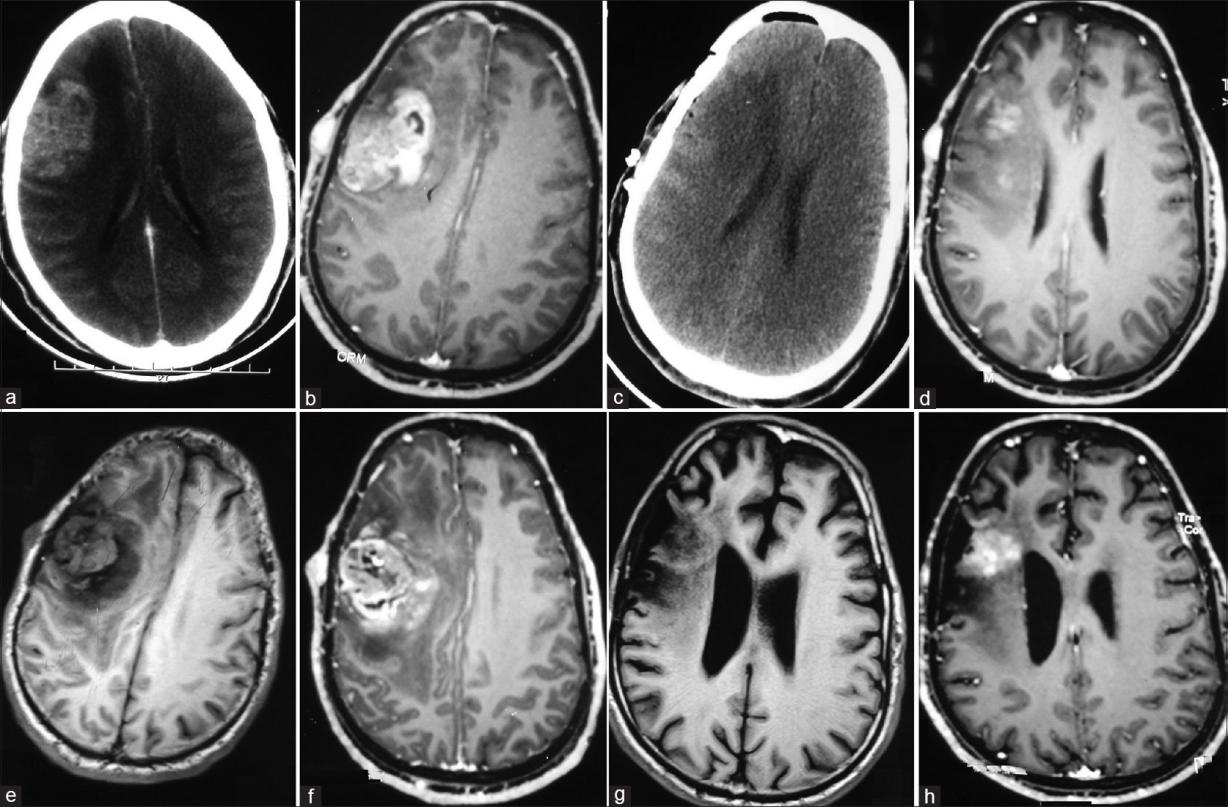

患者不同階段MRI

一名25歲的男性患者,有頭痛病史1年,且從幼兒時期起就經(jīng)常出現(xiàn)全身多發(fā)性腫脹,檢查發(fā)現(xiàn)多發(fā)性神經(jīng)纖維瘤(NF1)。之后的影像學(xué)檢查顯示,患者右額葉周圍有一個膠質(zhì)瘤病灶。在MRI上,T1加權(quán)上呈低密度,T2加權(quán)上呈高密度,在釓上呈均勻增強?;颊呓邮芰擞翌~葉開顱手術(shù)術(shù),術(shù)中見一淺表無包膜病變,累及軟腦膜,腫瘤幾乎得以全切。組織病理學(xué)檢查提示多形性黃色星形細胞瘤(PXA),免疫組化顯示腫瘤細胞膠質(zhì)纖維酸性蛋白陽性,皮下結(jié)節(jié)的組織學(xué)提示神經(jīng)纖維瘤。

由于未發(fā)現(xiàn)非典型細胞、高細胞或“壞死”,患者在術(shù)后未接受放射治療,且在術(shù)后未見不適癥狀。然而2年后,患者再次出現(xiàn)了高達15天持續(xù)頭痛癥狀。重復(fù)MRI檢查發(fā)現(xiàn)腫瘤復(fù)發(fā),有不均勻的強化、壞死和水腫。再次開顱手術(shù)顯示,腫瘤浸潤性生產(chǎn),有血管病變和壞死跡象,被證實為膠質(zhì)母細胞瘤。在腫瘤次全切后,患者接受了放射輔助局部放療(60gy)。在3年的隨訪中,病人暫無不適癥狀出現(xiàn),也沒有顯示任何復(fù)發(fā),但仍需保持定期隨訪。